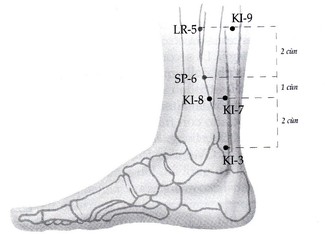

KI-9 zhubin, casa dell'ospite

Si trova a 5 cun sopra il malleolo interno, sul bordo all'interno del muscolo gastrocnemio. E' adatto nei casi in cui il deficit di Yin del Rene provoca ansia ed irrequitezza, è un punto rilassante anche nei casi di crisi di collera ed improperi. Apre il torace.

SP-6 sanyinjiao, incontro dei tre yin

E' un punto molto importante nei trattamenti Tuina e nel Qigong. Punto di riunione dei canali Yin del piede, Rene, Fegato e Milza, è un punto dotato di molteplici funzioni ed usato in diverse patologie. Il punto è soprattutto da utilizzare nei casi di Carenza nella Milza che si possono manifestare con feci poco formate e astenia; è quindi molto indicato per tonificare il Qi ed il Sangue. Sanyinjiao è utile anche per affrontare l'Umidità associata sia al Freddo che al Caldo nel Riscaldatore Inferiore; inoltre rafforza lo Yin , nutre il Sangue, mobilizza il Qi. In genere viene usato per eliminare le stasi di Sangue in relazione all'Utero. Esso si tratta anche per i dolori nel basso addome. Le combinazioni con cui viene usato sono quindi molteplici come sono molteplici i quadri in cui interviene una Carenza dello Yin. Molti autori non lo includono tra quelli del meridiano Yin Wei Mai.